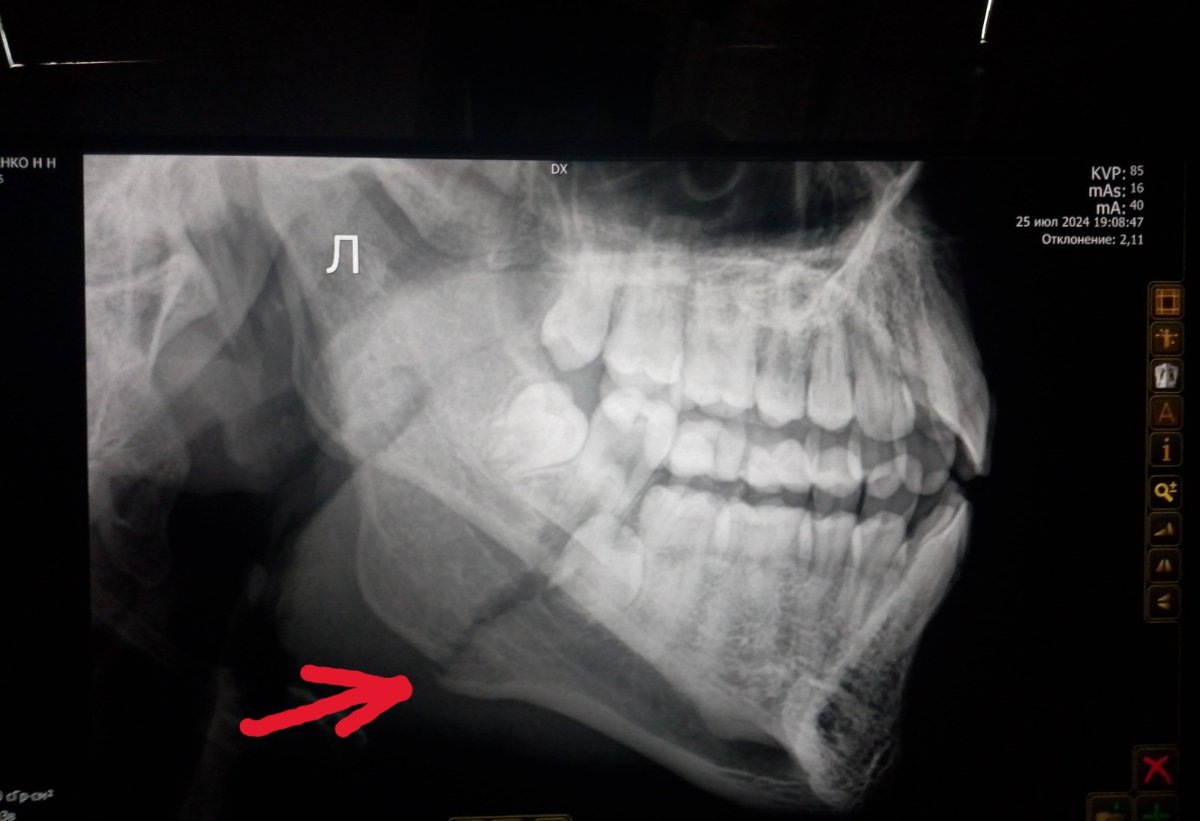

Задание   №   15 .

И  снова -  на   фото- рентгеновский   снимок ,   попробуйте   определить,

1. какая  ЧАСТЬ     тела    человека    на   снимке?

2. есть  ли   перелом?

Ответ  11.02.26      после  17.00   по   мскв  .

Крупный сустав . Коленный , кости голени и коленная чашечка . Есть перелом осколок небольшой.

Ответ  на   Задание   №   15 .

Крупный сустав . Коленный  округлость   верно  ощутили,   и  "крупный",   потому   как   ежели  смотрите    сами,   то   часто  визуализируете   и   то,   что   вне   снимка,   то  есть-  в  данном   задании- свод   черепа) ..  кости голени и коленная чашечка . Есть перелом верно!  осколок небольшой.

Скрытый текст

на   снимке  череп, челюстная   часть, боковая   проекция   и   перелом   нижней   челюсти ( указала  стрелочкой)

Кому  то    "вдарили"  в  челюсть..)